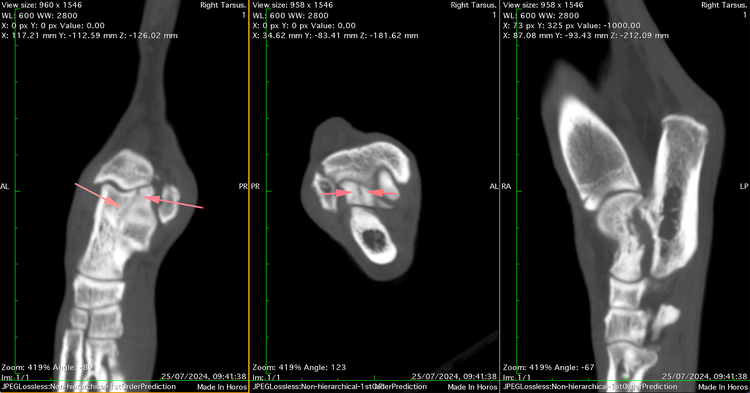

Specialist Orthopaedic surgeon Mark Bush took charge of the case and immediately identified a swollen and painful tarsus. CT imaging uncovered rare and complex fractures - one affecting the sustentaculum tali of the calcaneus and another involving the lateral ridge of the talus, extending into the joint.

Due to their unusual, non-displaced nature and challenging location, initial treatment was conservative. Lola’s limb was immobilised in a cast for six weeks with regular bandage changes. On re-examination, the calcaneal fracture was showing signs of healing; however, the talar fracture remained unchanged and Lola was still lame.

Surgical repair posed a dilemma. A standard lag screw technique was impractical - the fracture's location offered insufficient bone stock to safely countersink a conventional screw head, risking protrusion that could impinge on the tibial malleolus and compromise joint function. The salvage option, pantarsal arthrodesis, would have severely limited limb use and carries a significant complication rate - making it undesirable for such a young, active dog.

Instead, Mark and the team opted for an innovative solution: a headless compression screw (HCS), commonly used in human orthopaedic surgery for peri-articular fractures. The HCS generates compression along the fracture line thanks to its differential thread pitch, while its headless design allows full burial within the bone - eliminating the risk of joint interference.

The fracture’s small size, delicate location, and proximity to the joint meant precision was critical. To ensure accurate screw placement, Mark performed the surgery under real-time intra-operative imaging - a technique he has refined over more than a decade. Using continuous X-ray guidance allowed confirmation of ideal screw trajectory and depth, avoiding both joint violation and inadequate fracture engagement.